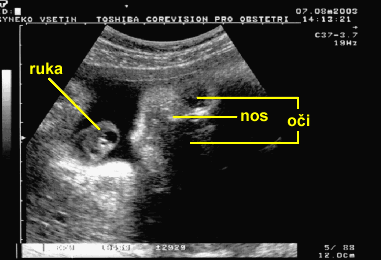

Ultrazvuková sonografie

Důležitá lékařská metoda pro zobrazení a vyšetřování vnitřních orgánů. Ultrazvukový signál vysílaný generátorem se po odrazu od různých tkání zachycuje mikrofonem a zpracovává se počítačem jako sonografický obraz. Takto se vyšetřují například ledviny, žlučník nebo srdce. Běžně se ultrazvukem vyšetřují budoucí maminky, kdy lékař na monitoru získá ultrazvukový obraz lidského plodu.